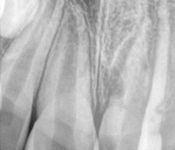

Pictured: Root Fractures/Splinting of Teeth and 1 Year Recall with Complete Root Formation

Parent of our 7-year-old patient was distraught by an injury that indicated horizontal root fractures in tooth #8 and tooth #9. Treatment involved splinting of teeth. After 1 year recall , the patient successfully had complete root formation.